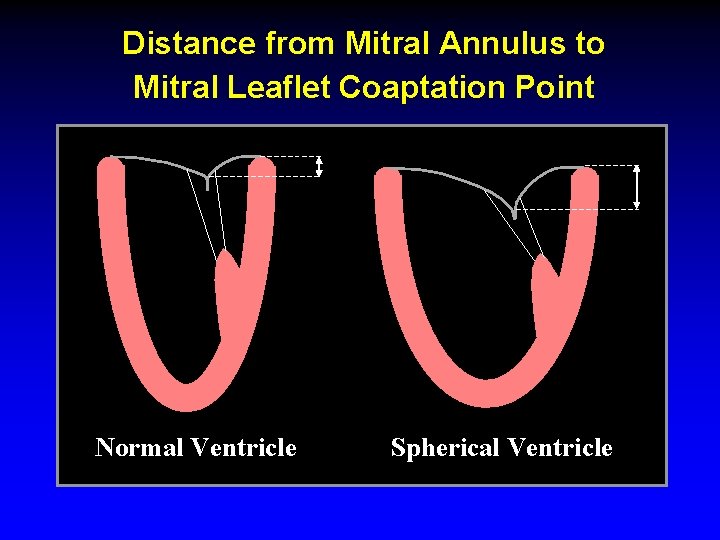

Distance from Mitral Annulus to Mitral Leaflet Coaptation Point Normal Ventricle Spherical Ventricle